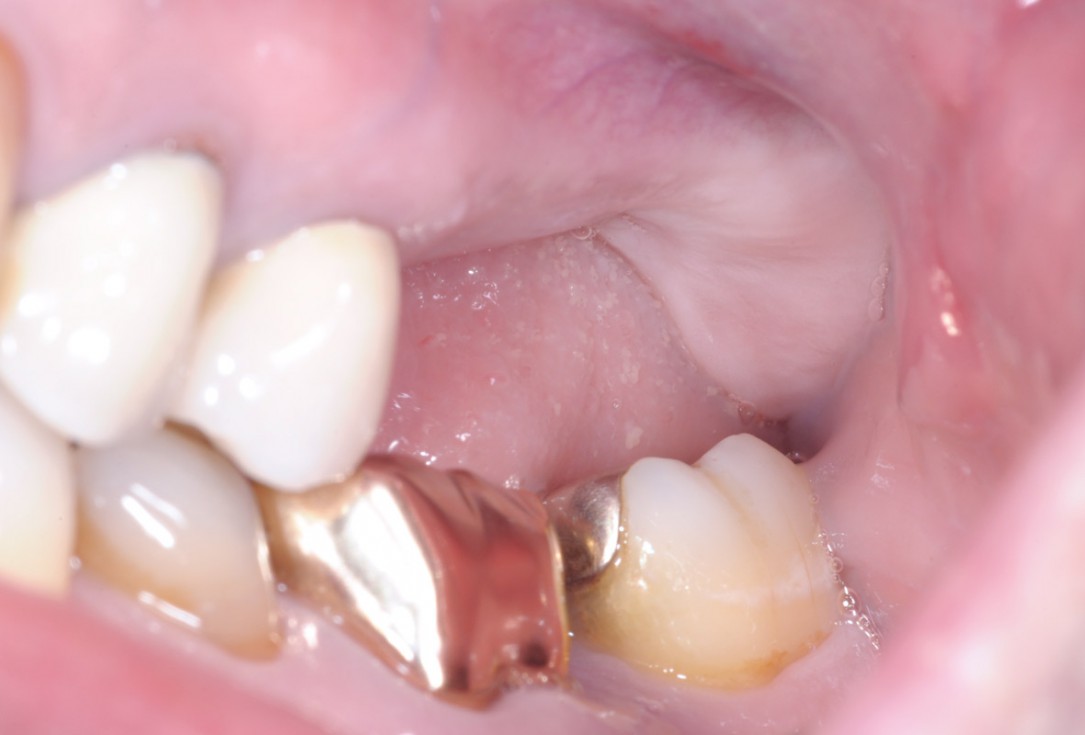

1/15 - Clinical situationTreatment of a combined horizontal and vertical bone defect in the maxilla with maxgraft® cortico in the allogenic shell technique - Dr. R. Würdinger